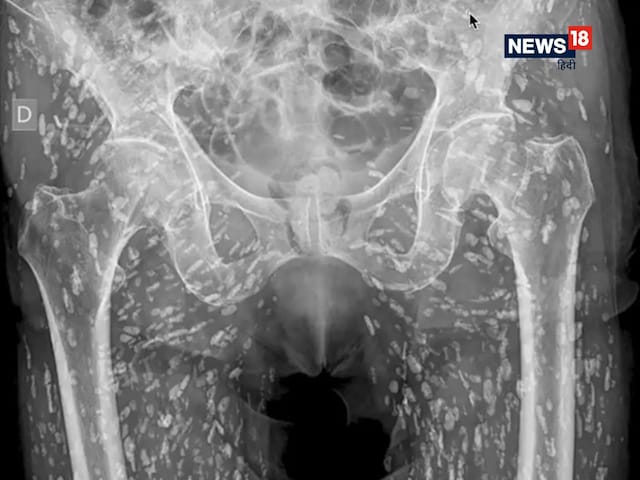

एक्स-रे में डॉक्टर को हैरान करने वाली चीज नजर आई. (फोटो: Twitter/EM_RESUS)

ट्विटर यूजर सैम घली एक चिकित्सक हैं. हाल ही में उन्होंने ट्विटर पर एक वीडियो पोस्ट किया है जिसमें एक एक्स-रे की फोटो है. ये किसी व्यक्ति के पेलविस वाले हिस्से का एक्स-रे है. आप देख सकते हैं कि पैरों में ढेर सारे निशान नजर आ रहे हैं. डॉक्टर ने बताया कि शख्स को कभी अपनी इस कंडीशन के बारे में नहीं पता था. उसे एक दिन दर्द हुआ तो वो इलाज के लिए अस्पताल पहुंचा. जब उसका एक्स-रे हुआ, तब डॉक्टर को ये दिखा, जिसे देखते ही उसके होश उड़ गए.

Always do your greatest to maintain clear, wash your arms, and by no means, ever, beneath any circumstances eat uncooked or undercooked pork https://t.co/68z3ffW8Uo